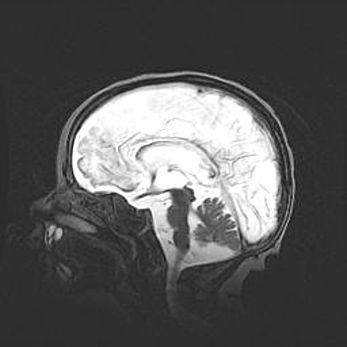

Церебральная ишемия II.

Возраст: 5 дней

Вес: 3400 г

Пол: женский

Окружность головы: 35 см

Срок гестации: 39 недель

Церебральная ишемия – это заболевание, характеризующееся недостаточностью (гипоксией) либо полным прекращением (аноксией) снабжения мозга кислородом по причине закупорки одного или нескольких сосудов. Это приводит к  что метаболическим расстройствам различной степени тяжести в тканях головного мозга, развитию коагуляционных некрозов и гибели нейронов.